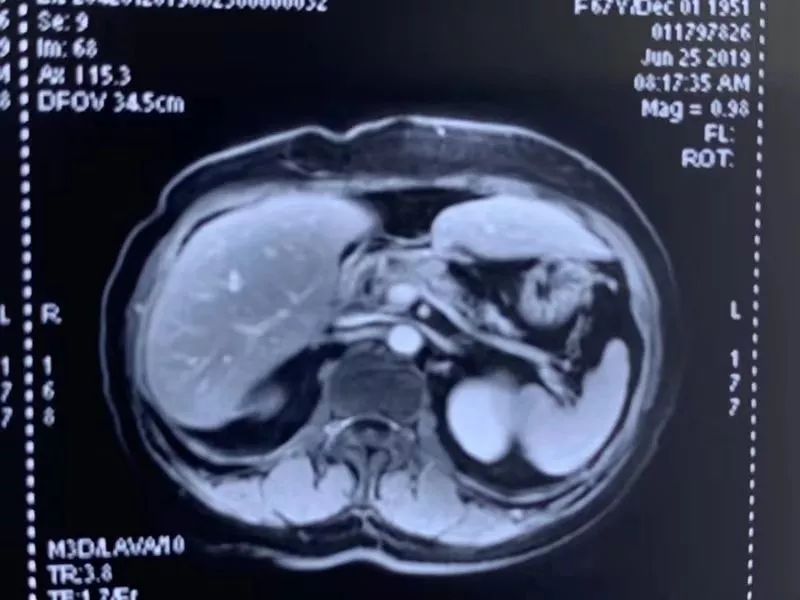

半年以后,成女士在当地医院复查,治疗效果非常好,这也十分出乎她的意料。复大肿瘤医院对成女士进行了随访,竟然发现胰腺没有任何异常,胰腺上竟然连一点肿瘤的影子都没有了,完全消失了。

复查报告

成女士的主刀医生,暨南大学附属复大肿瘤医院副院长牛立志教授表示:“这在医学上是一件非常了不起的事情。”一般做手术都会留个疤,消融之后也会有个坏死区,而纳米刀治疗过后,连一个坏死区都不存在了。